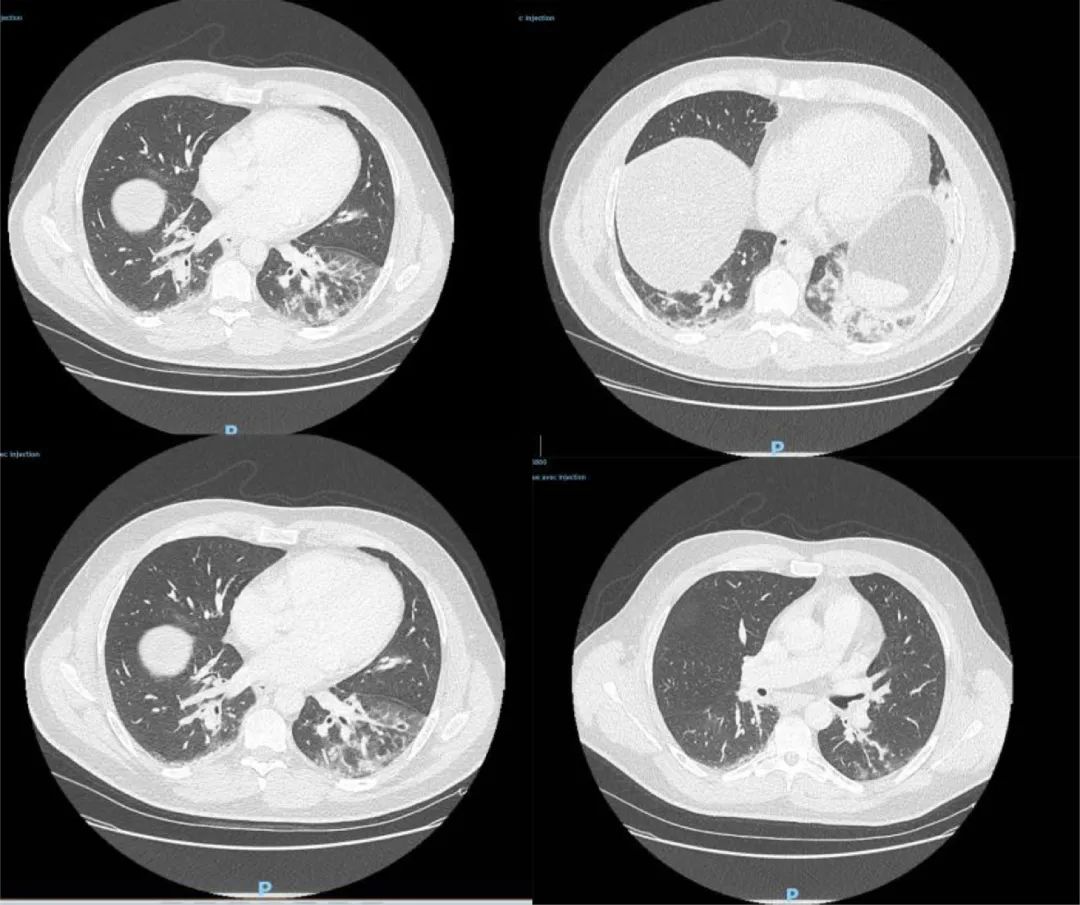

该男子职业为鱼贩,最近一次旅行是在2019年8月前往阿尔及利亚。他于去年12月27日到急诊室就医,CT检查显示双侧肺下叶呈现磨玻璃影,并伴有咯血、咳嗽、头痛及发热症状,且当时症状已持续4天。病患当天被收入重症监护室并进行治疗。

△图为病患CT检测影像